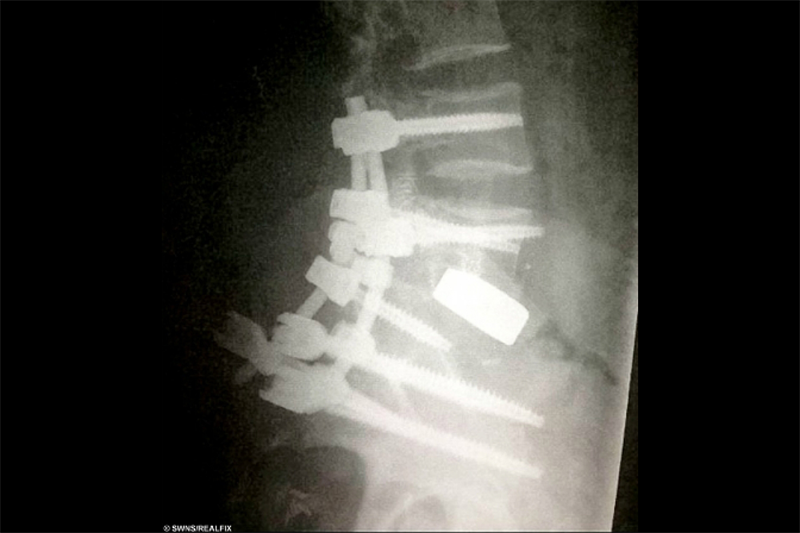

Xương sống của Beth được thay thế bằng loại ốc vít titan. Ảnh: SWNS.

Beth sau đó đã trải qua một ca mổ kéo dài 11 giờ. Bác sĩ tại Bệnh viện chỉnh hình Hoàng gia và Bệnh viện UCL đã cứu mạng cô khi tách rời xương sống với xương chậu, và thay thế nó bằng loại ốc vít titan.